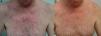

The papulopustular rash was treated as soon as possible to avoid having to discontinue anti-EGFR therapy due to toxic effects. Fig. 2 shows the treatment algorithm used at our department to treat papulopustular rash according to severity. All patients with a grade 2 or 3 rash were treated with oral tetracyclines (Fig. 3A), which achieved adequate control (Fig. 3B). Isotretinoin was needed to treat 3 patients with a more refractory skin rash, and a good response was obtained in 2 of these. The third patient did not tolerate this treatment, leading to discontinuation of anti-EGFR therapy.